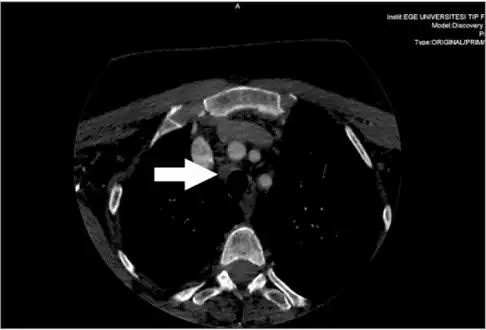

Metastatic central lymph node of a medullary thyroid cancer case

Medullary thyroid carcinoma on ultrasound with typical small calcifications (arrows)

Diagnosis is primarily performed via fine needle aspiration of the lesion of the thyroid to distinguish it from other types of thyroid lesions.[6] Microscopic examination will show an amyloid stroma with hyperplasia of parafollicular cells.